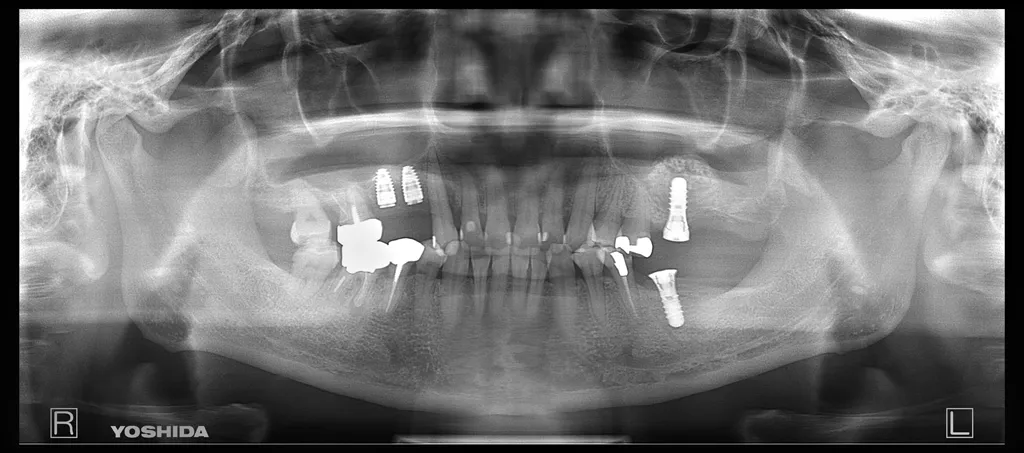

インプラントの症例

49歳 女性

- before

治療本数:4

治療部位:15,14,11,26,36

治療方法:通常埋入+左側サイナスリフト(26)+GBR

種類: ITI(ストローマン)+ジルコニア